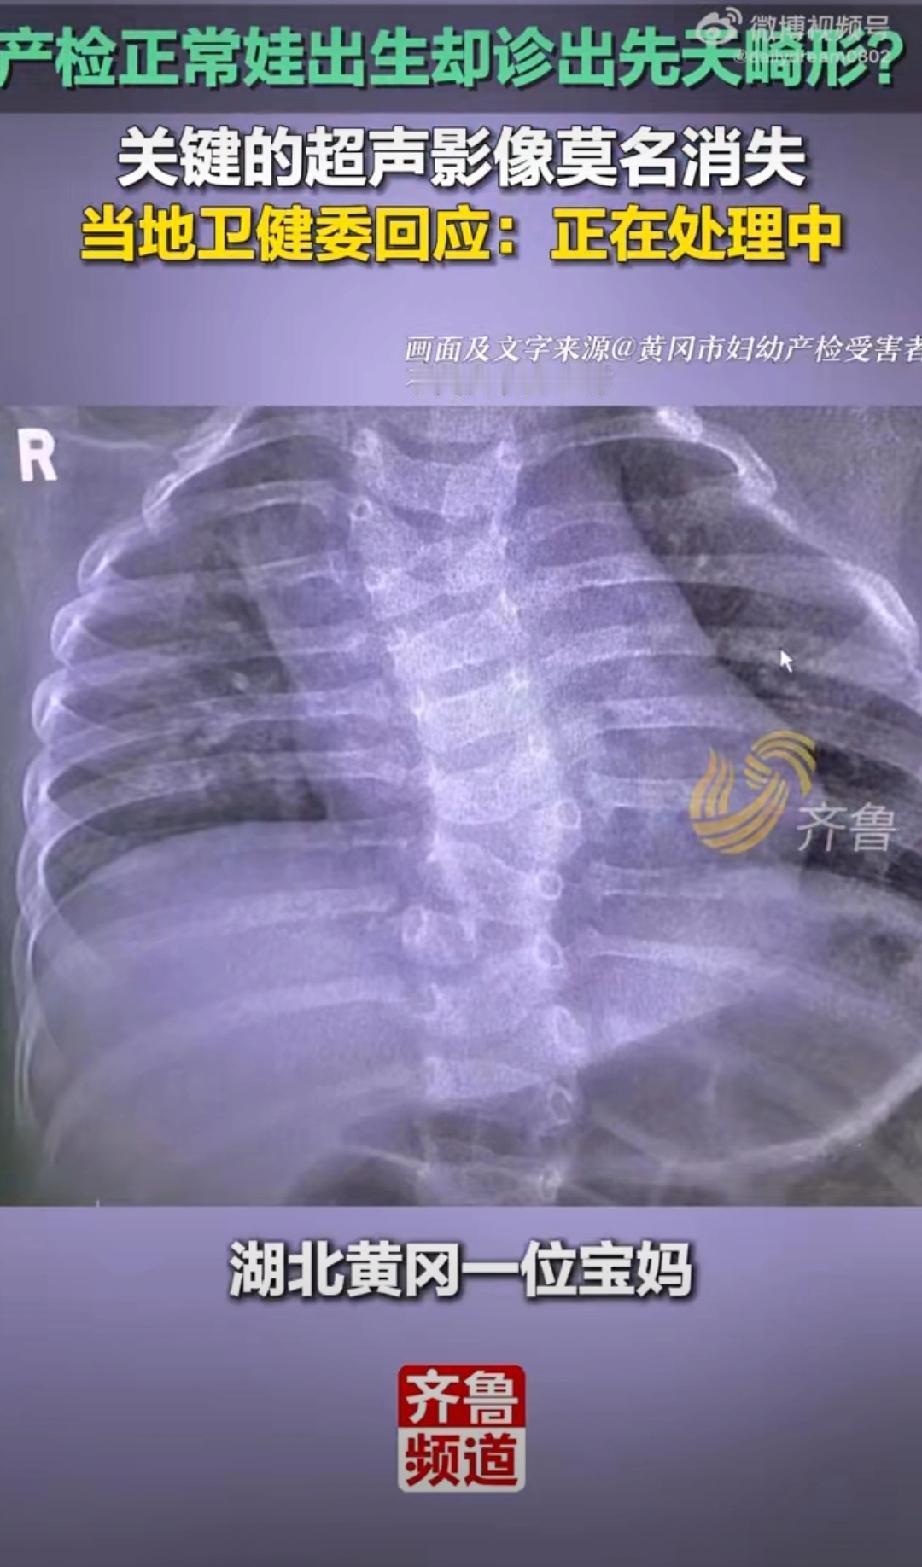

产检正常孩子却先天畸形,官方通报了,三个问题直指核心,但评论区有些气人: 1. 医生无资质:操作医生李某虽有《医师执业证》,但未取得产前筛查相关的《母婴保健技术考核合格证》,属于违规执业; 2. 操作不规范:未按国家指南要求拍摄脊柱全段关键切面,直接导致畸形漏诊; 3. 影像资料缺失:畸形最严重的颈胸段超声影像未留存,严重违反诊疗规范。 涉事人员已被处理:分管副院长被立案调查,超声科主任被免职,涉事医生被警告并调离岗位。 这个代价太过沉重了,再多的处罚与赔偿,都换不回健康孩子。愿严查医疗漏洞、严守执业规范,让所有家庭都能迎来平安健康的新生命产检诊断 胎儿畸形筛查 儿童畸形